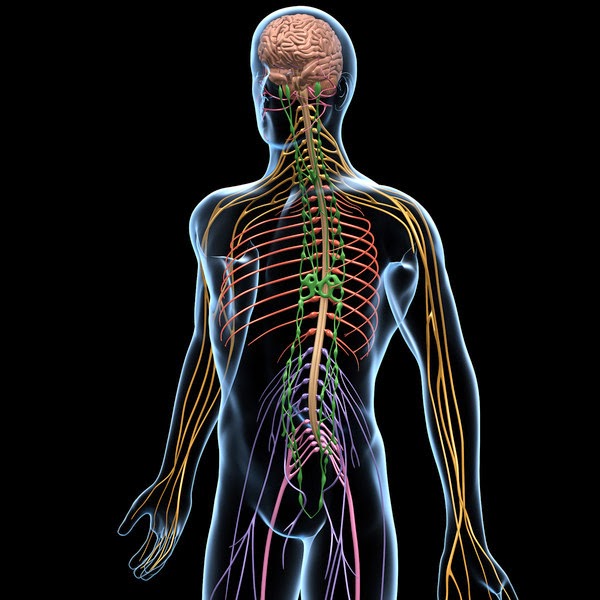

Levando em consideração que o alvo da maioria dos inseticidas utilizados

é o sistema nervoso, esses não sendo específicos para insetos, não é difícil

correlacionar a ingestão de alimentos contaminados aí por uma vida toda, com os

altos níveis de problemas relacionados ao sistema nervoso em geral, os quais podem

abranger desde depressão, doenças degenerativas, falta de memória, falta de

audição, visão entre outros até paralisias e problemas cardíacos. Afinal, o

sistema nervoso controla todo o nosso corpo, problemas no funcionamento dele

podem acarretar os mais diversos problemas, os quais raramente alguém pode pensar

que pode ser por culpa dos alimentos.